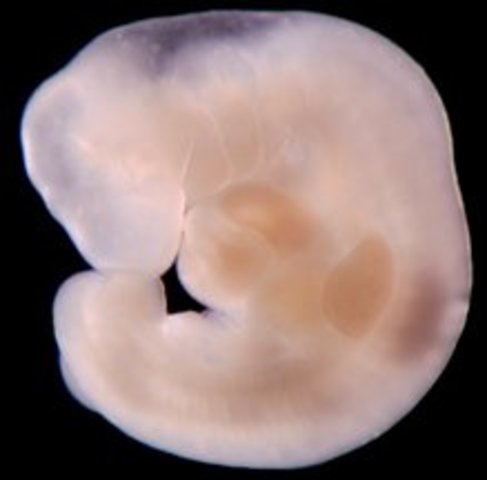

• Week 8

Week 8

Embryo is now 3/4 inch, elbows and toes are becoming visible, starts practicing movements, stomach is being made and face is taking shape.